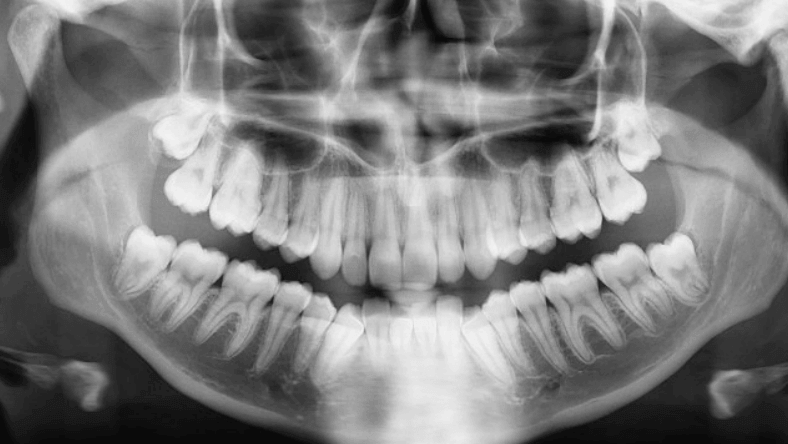

Dental X-Ray

Specialist dental X-rays such as OPG and Lat Ceph are designed to image the teeth and jaw, plus any surrounding facial structure required to be visualised by your referring physician. These are commonly done to aid in the planning of orthodontic treatment, assessment of wisdom teeth or for a general overview of the teeth and the bone that supports the teeth.

An OPG is a panoramic or wide view X-ray of the lower face, that displays all the teeth of the upper and lower jaw on a single film. It shows the number, position and growth of all the teeth including those that have not yet surfaced or erupted. Dentists may at times take images of an individual tooth or group of teeth, this is different in that it images all teeth in the jaw in succession.